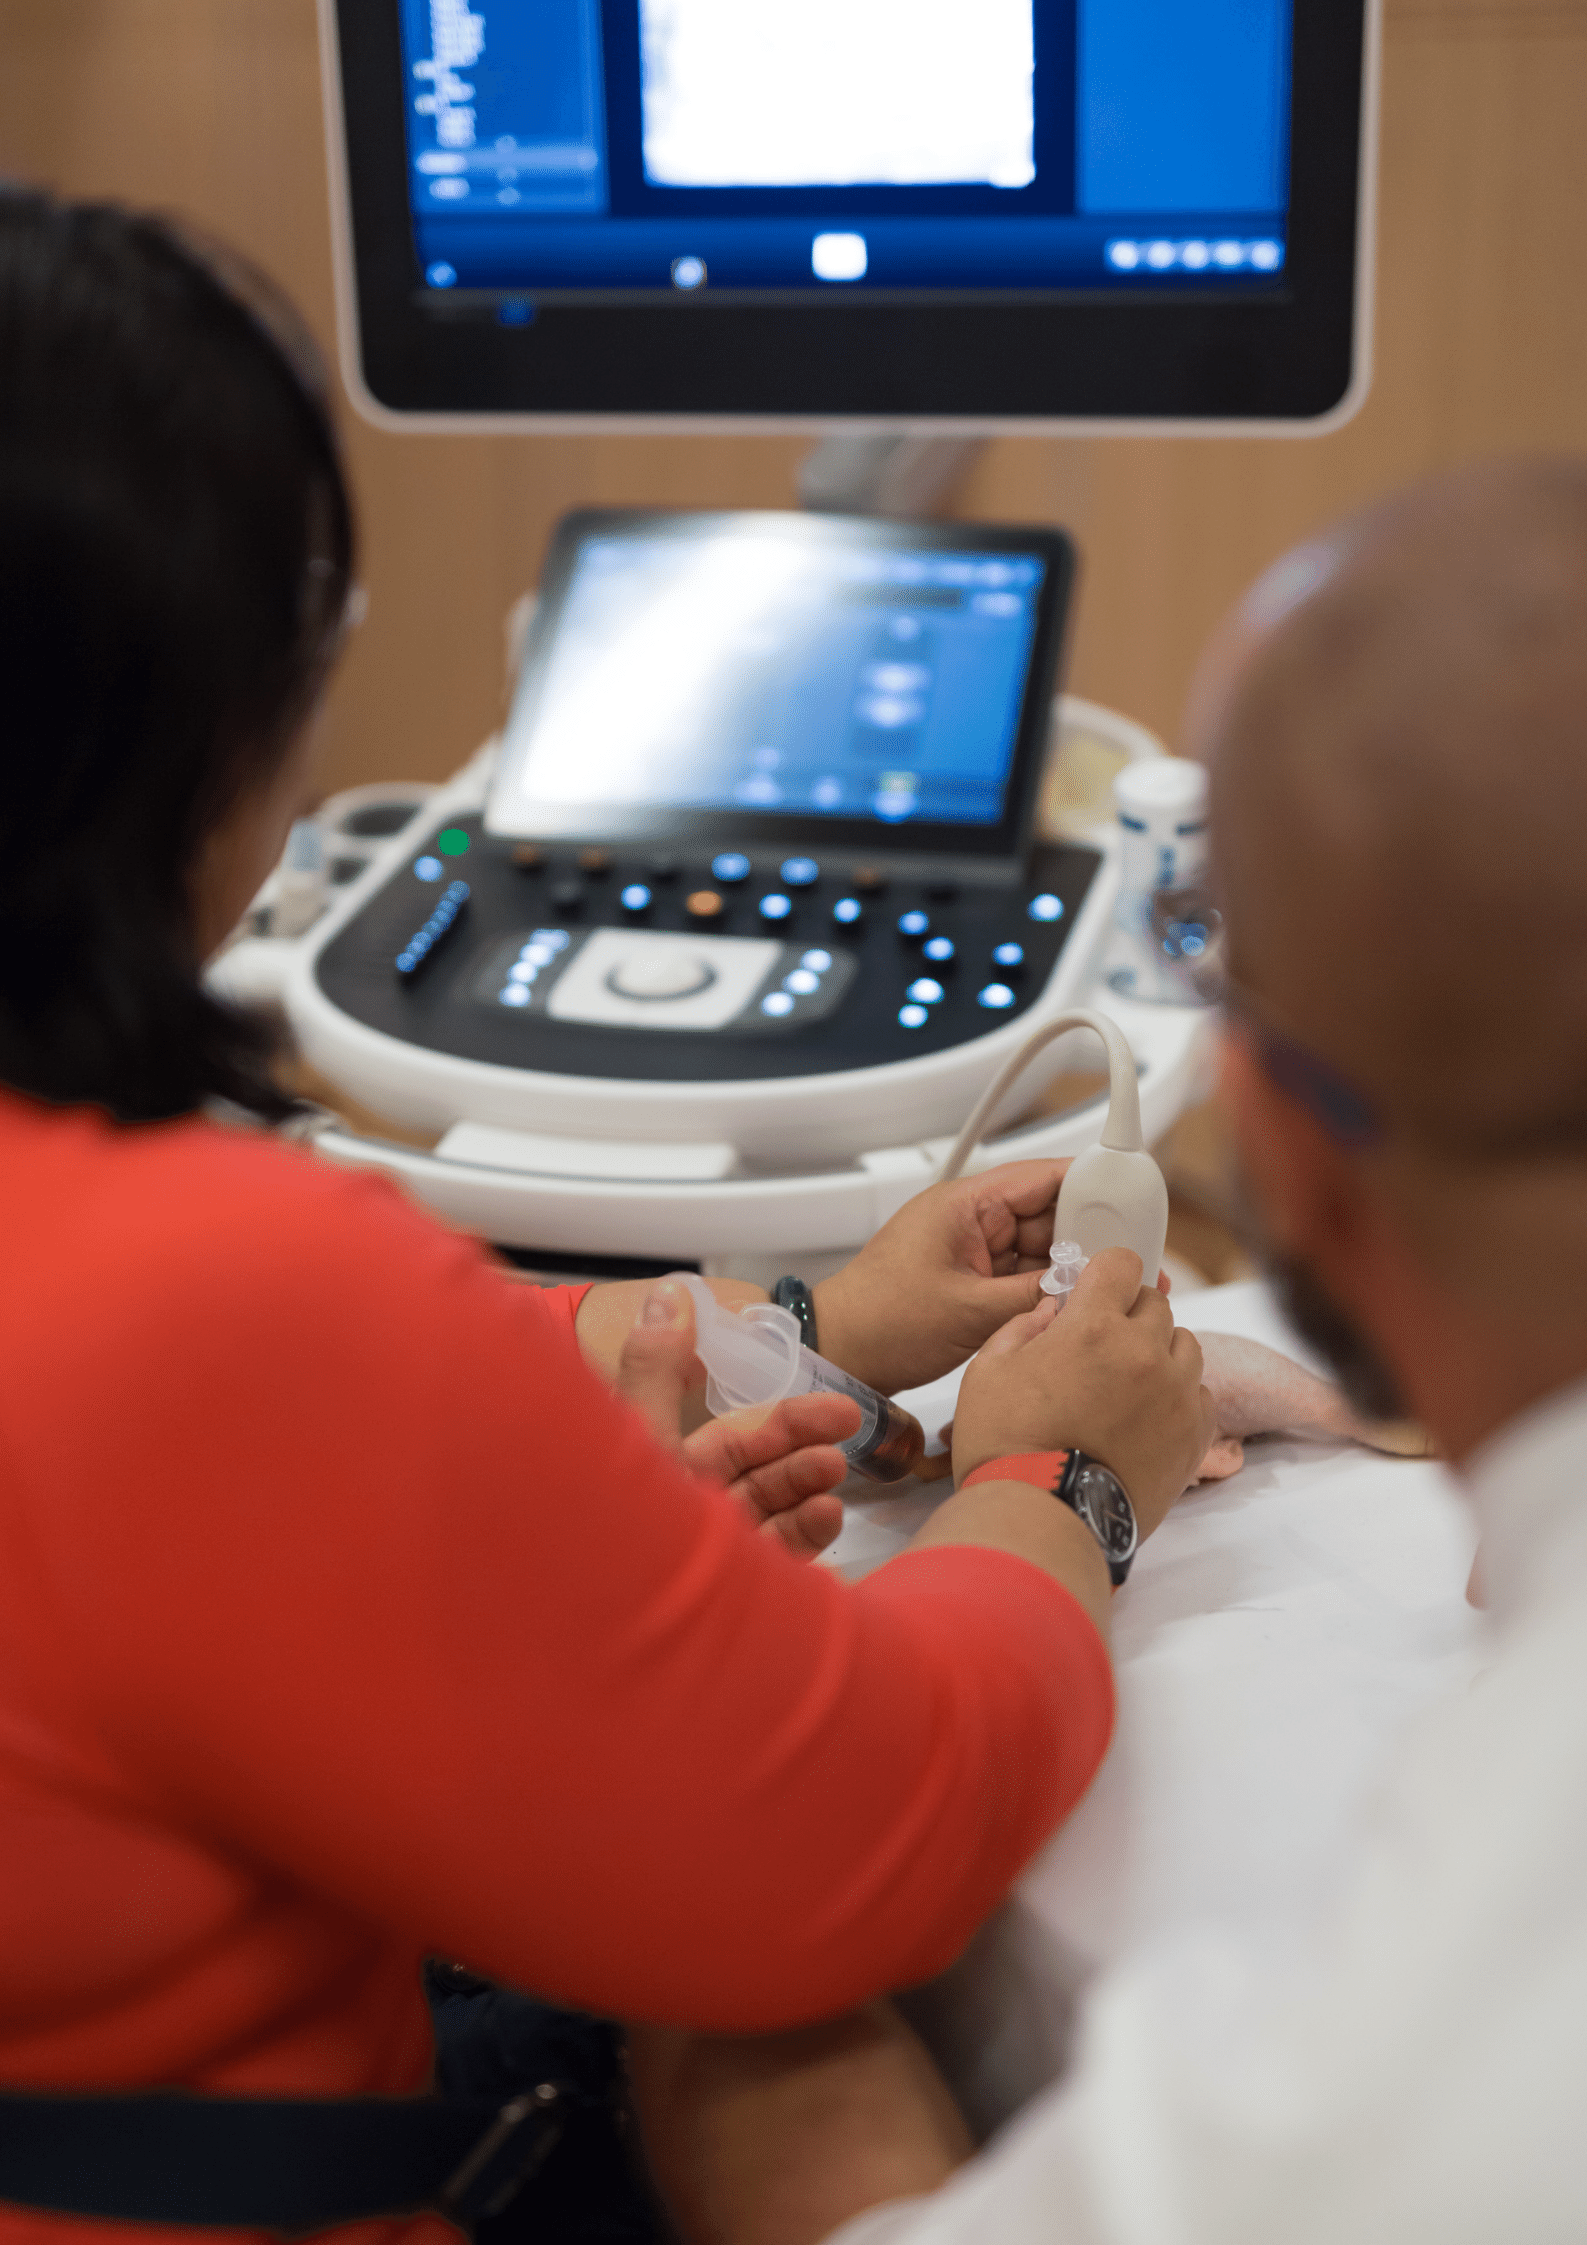

Interventional Radiology (IR) is a medical specialty that performs various minimally-invasive procedures using medical imaging guidance. IR performs both diagnostic and therapeutic procedures through very small incisions or body orifices.